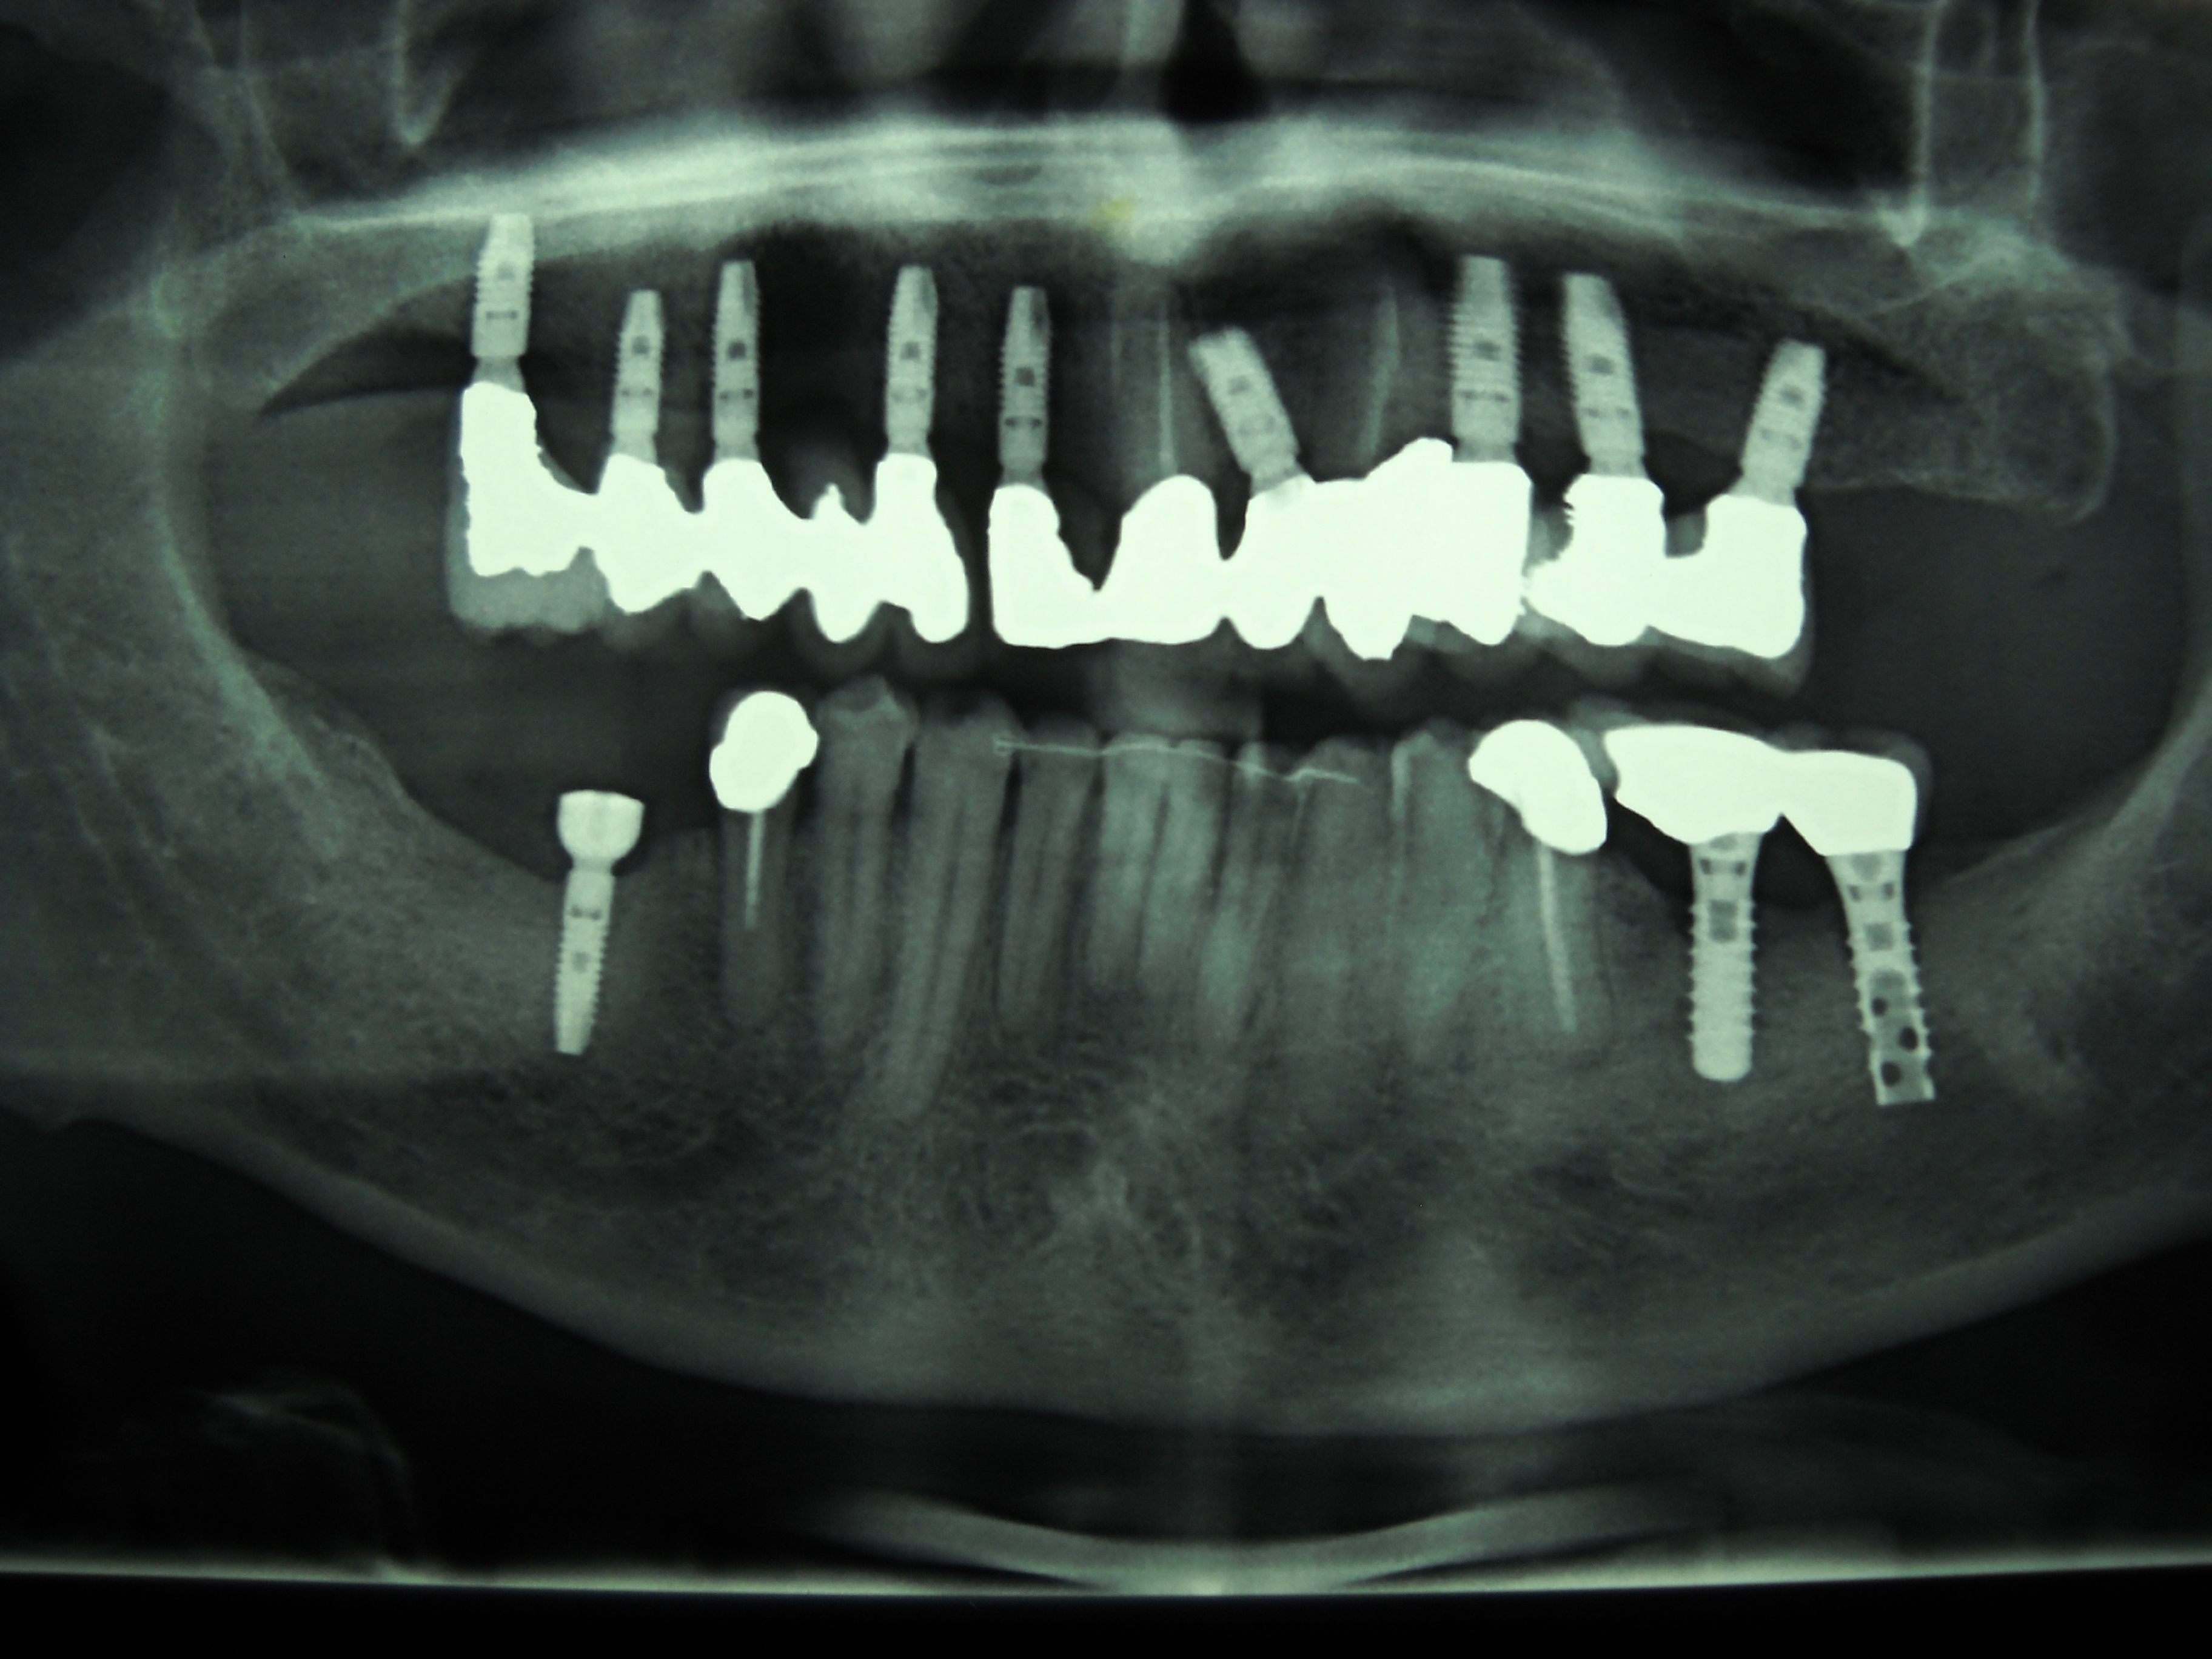

Riabiliatazione completa dell'arcata superiore con l'applicazione di 9 impianti, con rialzo seno mascellare sx e rigenaritiva con bios e membrane.

Prima: applicazione 9 impianti

Dopo: risultato estetico e funzionale